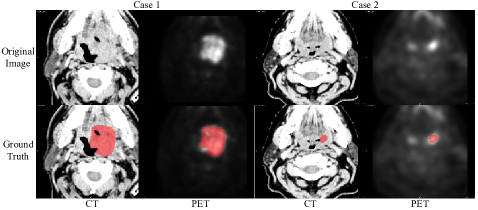

Table 1 and Figure 2 present the quantitative and qualitative results on the testing set, respectively. The proposed method achieved the 2nd place on the official leaderboard, which is also very close to the 1st-place performance. The segmentation results have better precision but inferior recall, indicating that most of the segmentation results are right but some tumors are missed by the method.

Refer to caption

Figure 2: Visual examples of segmentation results from testing set.